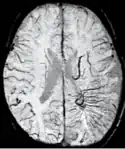

Diffusion weighted imaging offers a powerful means to detect acute stroke. Although it is well known that gradient echo imaging can detect hemorrhage, it is best detected with SWI. In the example shown here, the gradient echo image shows the region of likely cytotoxic edema whereas the SW image shows the likely localization of the stroke and the vascular territory affected (data acquired at 1.5 T).

The bright region in the gradient echo weighted image shows the area affected in this acute stroke example. The arrows in the SWI image may show the tissue at risk that has been affected by the stroke (A, B, C) and the location of the stroke itself (D). The reason that we are able to see the affected vascular territory could be because there is a reduced level of oxygen saturation in this tissue, suggesting that the flow to this region of the brain could be reduced post stroke. Another possible explanation is that there is an increase in local venous blood volume. In either case, this image suggests that the tissue associated with this vascular territory could be tissue at risk. Future stroke research will involve comparisons of perfusion weighted imaging and SWI to learn more about local flow and oxygen saturation.